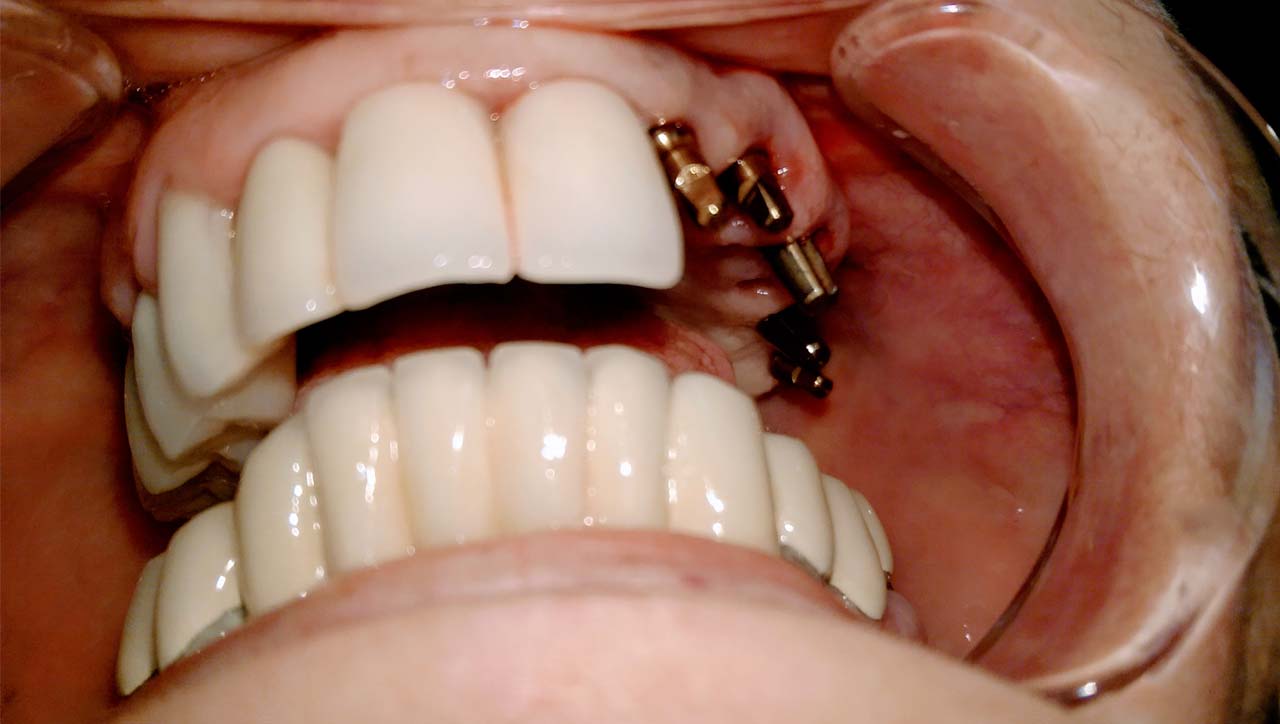

Teljes fogatlanság helyreállítása 2 nap alatt

Teljes fogatlanság helyreállítása 2 nap alatt azonnal terhelhető svájci IHDE implantátumokkal és PMMA műanyag hidakkal. Intraorális szkennerrel vettünk lenyomatot az implantáció után, és erre a digitális mintára készítette el a fogtechnika a hidak digitális tervezését, majd faragta ki műanyagból. Ezt a gyors munkát az azonnal terhelhető implantátumok és a digitális lenyomat, tervezés segítségével tudtuk megcsinálni mindössze 2 nap alatt. Dr. Kelemen Péter és a Symbion Fogtechnika munkája.